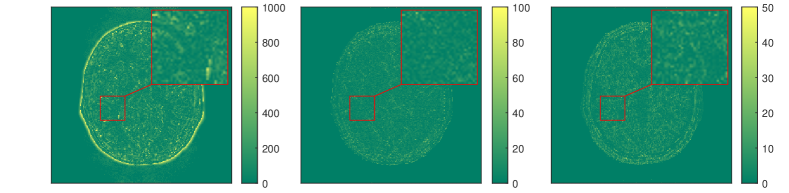

In [178] a line-search strategy is proposed to find the step size-parameter that has to be adjusted in dependence of the unknown Lipschitz constant of in order to guarantee a sufficient descent of the objective in each step of the algorithm. The overall method alternates between the three optimization steps and is shown to converge against a limiting-stationary point. Prototypical numerical results from [178] are depicted in Figure 9, where the dictionary learning approach is compared against the pure Levenberg-Marquardt method from Section (2.2) and the BLIP method in [52]. Here the number of image frames was chosen to be and the under-sampling factor is 16. Moreover small complex noise was added to the under sampled Fourier data. The details can be found in [178] where also extensions of the methods are discussed.